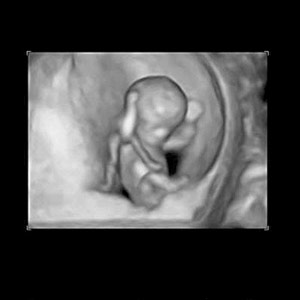

Yes, it's bogus. A 12 week old fetus does tend to be difficult to locate among the blood, tissue and blood clots that come from a miscarriage, being that they are so small. But, when the fetus/embryo is found, all you have to do is look at the arms and know there is no possible way it can rub its eyes. The arms are not long enough.

????....so this image from Parent magazine of an 11 week old fetus is bogus?....

ss_week11_3D_ultrasound.jpg

First Trimester Fetal Development Images of Your Growing Baby